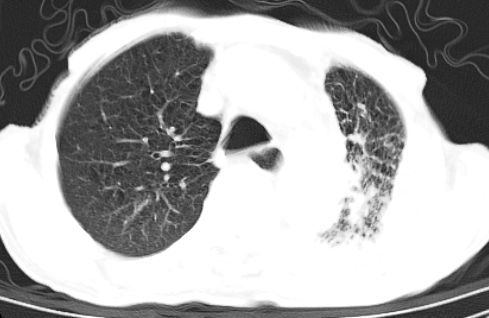

标题: CT10141:男、84岁,咳嗽、咯血1年。 [打印本页]

标题: CT10141:男、84岁,咳嗽、咯血1年。

支持左侧中央型肺癌伴下叶肺不张\\纵隔淋巴结转移.左侧包裹性胸腔积液\\心包积液.左侧少量胸腔积液..慢性支气管炎伴部分间质纤维化.

支持:左侧中央型肺癌伴下叶肺不张\\纵隔淋巴结转移.左侧包裹性胸腔积液\\心包积液.左侧少量胸腔积液..慢性支气管炎伴部分间质纤维化.另:支气管分支根部明显阻塞 狭窄,内膜凸凹不平,提示内膜增生物。

咯血病史较长,左肺下叶实变,体积未明显缩小,隐约可见血管影及坏死阴影,双肺门及纵隔淋巴结增大,心包增厚积液,纵隔右移位,单侧胸腔积液,首先考虑:大叶型肺泡癌伴纵隔心包转移。